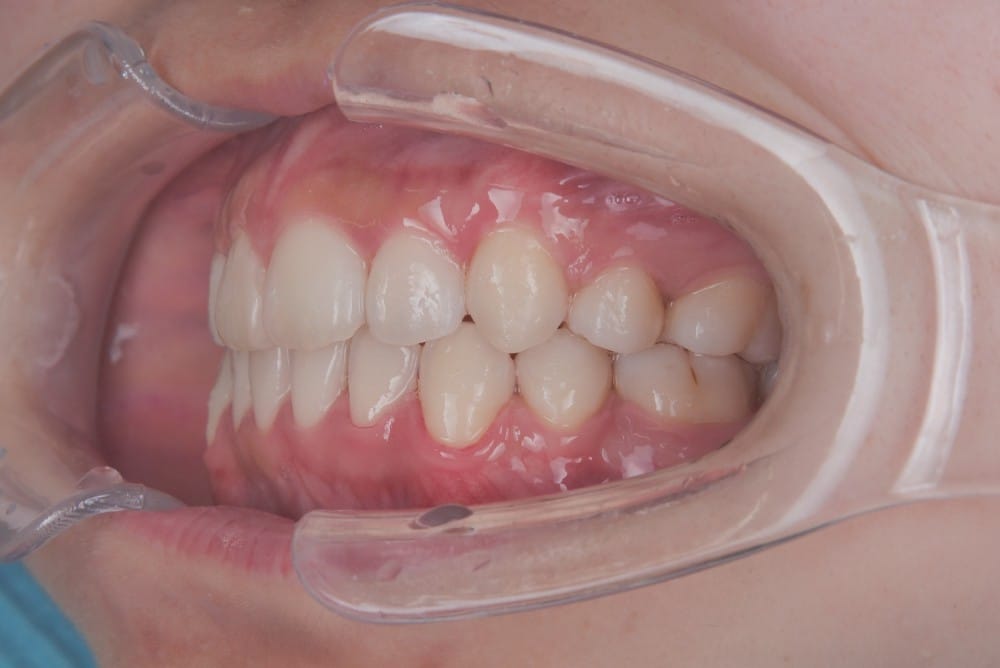

実際の治療前後の写真

before

after

前歯を数ミリ後退させるだけでも、唇の位置は明確に変わります。

横顔ではEラインとの距離が縮まり、「横顔がすっきりした」「口が自然に閉じられるようになった」と感じられる方が多いです。

また、歯の角度を適切にコントロールすることで、歯茎ごと前に出ているように見えていた印象が改善するケースもあります。歯列が原因であれば、外科手術を行わずに目標に近づける可能性が高いのです。